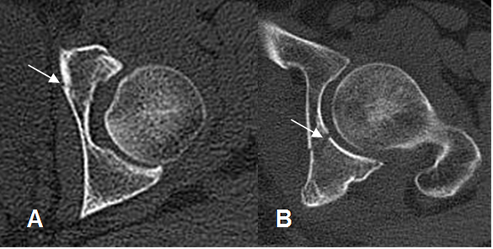

Fig 63 B. Fractura del acetábulo. Categoría II.

A: Rx AP. Fracturas lineales en el techo acetabular y el ramo isquiopúbico.

B: TAC reconstrucción coronal y TAC axial. Fractura del techo acetabular, con compromiso de la columna anterior (Flecha gruesa) y ambas paredes (Flechas delgadas).